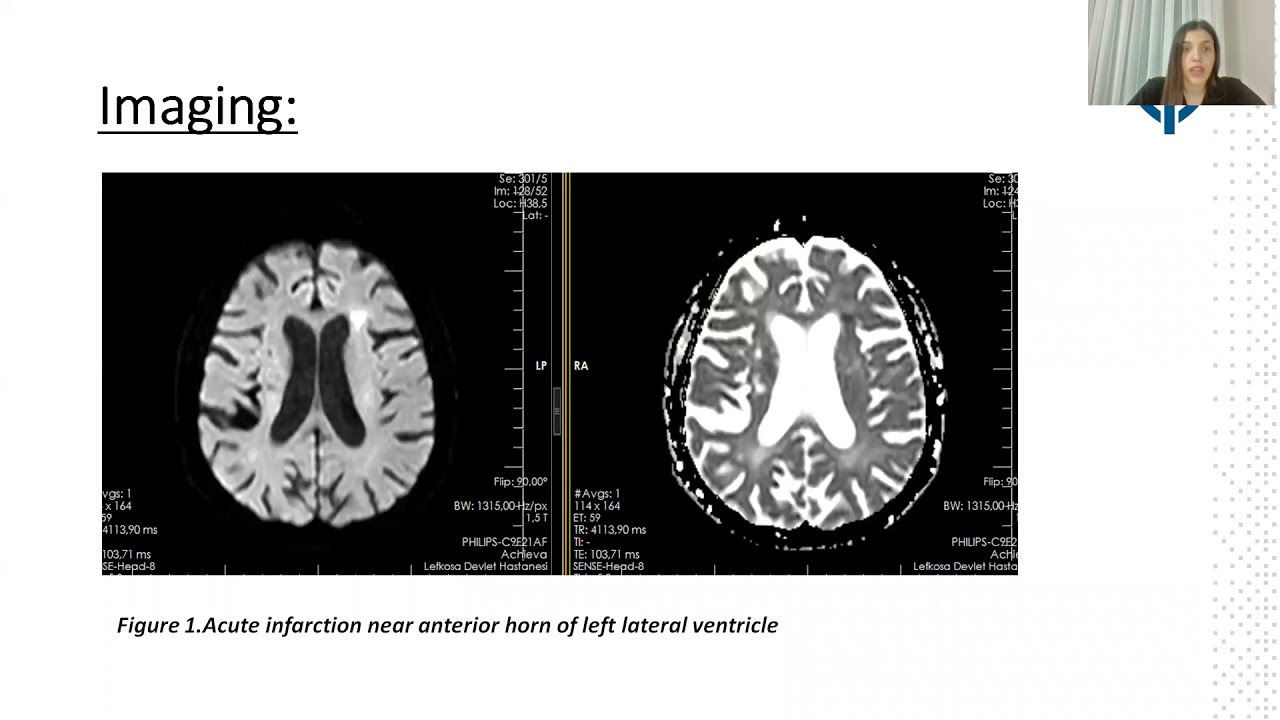

Left Atrial Appendage Occlusion For Resistant Stroke Despite Concomitant Oral Anticoagulation And Antiplatelet Therapy

By: Nur Shanableh, Dr Burhan Nalbantoglu Public Hospital, Nicosia, Cyprus